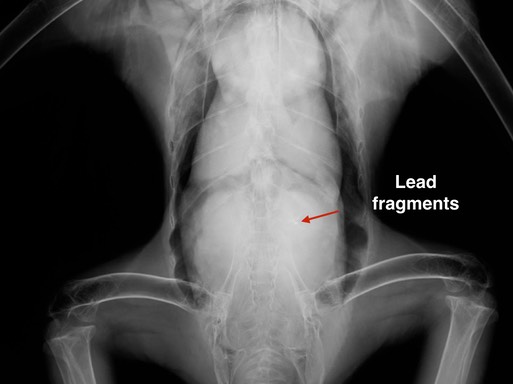

Bald Eagle 20-004

The eagle’s right wrist was completely shattered. There were also lead fragments in his stomach. We may have been able to successfully treat the lead poisoning, but the wing was not salvageable and the eagle was euthanized.